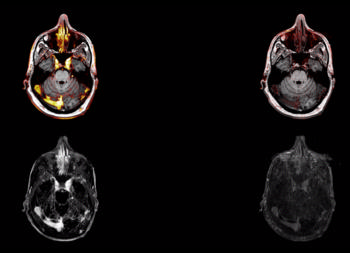

Figure 2. Imaging protocol used with 3 different MR series at different contrast doses.